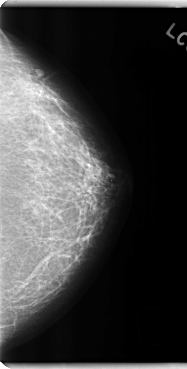

C_0201_1.LEFT_CC

LEFT_CC LINES 4792 PIXELS_PER_LINE 2424 BITS_PER_PIXEL 12 RESOLUTION 50 NON_OVERLAY